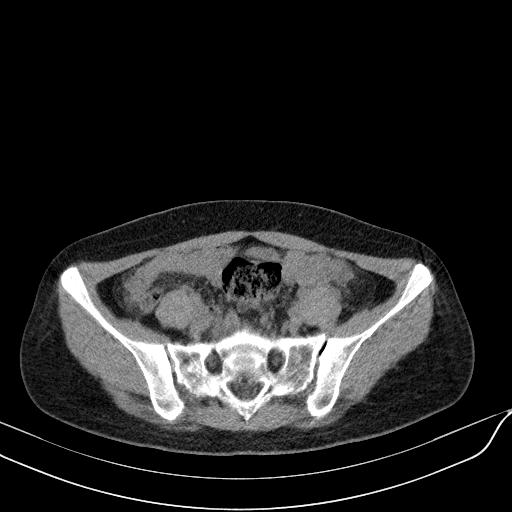

标题: CT23965:无外伤史,下腹痛 [打印本页]

标题: CT23965:无外伤史,下腹痛

肠道未准备,继续往下扫,乙状结肠占位不排除。建议钡灌或结肠镜检查。

乙状结肠占位不排除

未见明显异常改变,做个气钡双重造影除外一下结肠病变,无外伤史为啥不常规喝泛影葡胺水对比剂再扫ct呢?

扫描时应做肠道准备,口服稀释造影剂。

回肠间质瘤?

肠道肿瘤,建议行钡剂灌肠检查。